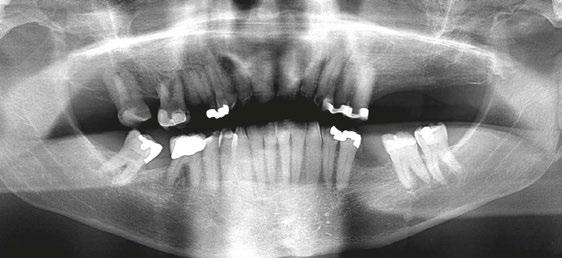

A 64-year-old male presented to the dental clinic for extraction of non-restorable maxillary left first, second, and third

Figure 1: The patient’s panoramic radiograph upon initial consultation

molars in January 2019. The past medical history was significant for cystic fibrosis and depression. He had an allergy to sulfa medications and was taking the following medications: Pulmozyme® (dornase alpha), testosterone, prednisone, and nifedipine. The patient presented with a chief complaint of “I didn’t think I was going to live this long with cystic fibrosis, but I did, and now I am ready to take care of my needs.” The clinical examination was significant for a grossly carious dentition in need of repair (Figure 1). After reviewing several options, it was decided to extract the non-restorable left maxillary first, second, and third molars and to restore the maxillary left first and second molars with fixed implant-retained restorations. With potential healing concerns secondary to his cystic fibrosis, the addition of platelet-rich fibrin (PRF) was discussed. The patient was taken to the surgical operatory where the blood pressure was taken, a pulse oximeter placed, and an IV was started using a 21-gauge butterfly catheter in the right antecubital fossa. PRF protocol was followed using Intraspin® centrifuge (BioHorizons; Birmingham, Alabama), and anesthesia was maintained thereafter using a balance technique. Maxillary left first, second, and third molars were surgically removed, and the resulting extraction sockets were curetted free of granulation tissue. PRF clots and membranes were prepared as described by Choukroun, et al.15 The PRF was mixed 50/50 with MinerOss® mineralized allograft cancellous bone particles (BioHorizons; Birmingham, Alabama) resulting in a “sticky bone preparation” that was placed in the maxillary left first and second molar sockets (Figure 2). Two PRF membranes were placed across the extraction sites (Figure 3), and 3-0 PTFE interrupted sutures were placed affording good wound apposition (Figure 4). Adequate soft tissue healing was observed at a 3-week postoperative check.

The patient returned a year later in December 2019 after receiving bilateral knee replacements. He wanted to fully recover and rehab from the knee reconstructive surgery before having his dental implants placed. A panoramic radiograph and CBCT were performed with Carestream CS9300 (Carestream

Atlanta, Georgia) (Figures 5 and 6). The patient was taken to the oral surgical suite where a 23-gauge butterfly intravenous catheter was started in the right antecubital fossa, and anesthesia was maintained thereafter with a balance technique. A crestal incision was performed, and a full-thickness flap was reflected. Osteotomies were performed using appropriate drills. A BioHorizons Tapered Pro 4.2 mm x 12 mm implant was placed at tooth No. 14 position, and a BioHorizons Tapered Pro 5.2 mm x 10.5 mm implant was placed at tooth No. 15 area. Both implants were placed with greater than 35 ncm torque values (Figure 7). Gingival former healing collars were placed for single stage implant surgery. The wound was closed using interrupted sutures, and the patient was discharged in the care of a family member.

One can appreciate the decrease in bone density in the ungrafted posterior maxilla (Figure 8) and the moderately more dense appearance in the grafted site where the PRF graft changed the local topography (Figure 9). The implants have subsequently integrated, and the patient is waiting to return to the restorative dentist when “he feels comfortable returning to a dentist office post-COVID” for a planned splinted cement-retained restoration. In the posterior maxillary region, this restoration would allow a greater chance of success in the D3 bone.

Figure 7: Postoperative periapical radiograph immediately after implant placement Figure 8: Notice the lack of bone density in the ungrafted maxillary left third molar socket Figure 9: The PRF/cortical cancellous bone graft increased the density of the implant site as seen in the postoperative transaxial CBCT view